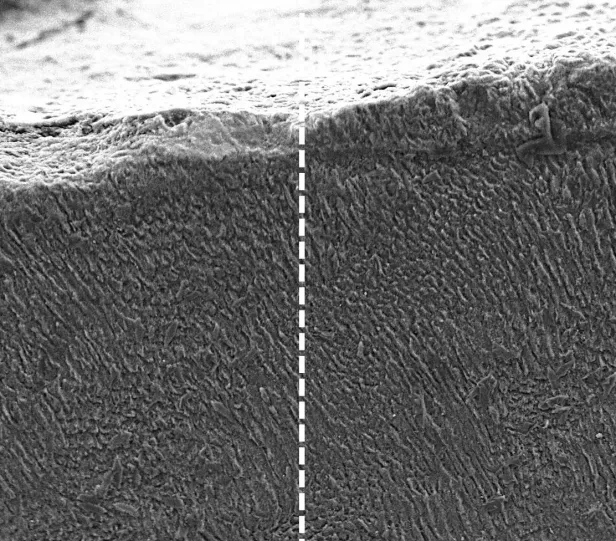

Vergleich der Zähne vor und nach der Behandlung mit Keratin.

Vergleich der Zähne vor und nach der Behandlung mit Keratin

Durch Keratin kann die Struktur und Funktion von Zahnschmelz nachgeahmt und so eine dichte Schutzschicht aus Mineralien gebildet werden. Dadurch werden freiliegende Nervenkanäle, also jene Ursache für Schmerzen, abgedichtet.